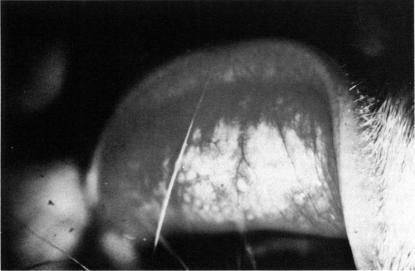

Giant papillary conjunctivitis is a syndrome found frequently as a complication of contact lenses. Many variables can affect the onset and severity of the presenting signs and symptoms. Rigid gas permeable contact lenses appear to result in less severe signs and symptoms, with a longer time before the development of giant papillary conjunctivitis. Nonionic, low-water-content soft contact lenses tend to produce less severe signs and symptoms than ionic, low-water-content soft contact lenses. Enzymatic treatment appears to lessen the severity of signs and symptoms. The association of an allergy appears to play a role in the onset of the severity of the signs and symptoms but does not appear to affect the final ability of the individual to wear contact lenses. Using multiple treatment options, such as changing the polymer to a glyceryl methyl methacrylate or a rigid lens, or utilizing a soft lens on a frequent-replacement basis, can result in a success rate of over 90%. In individuals who still have a return of symptoms, the use of topical mast cell stabilizers or a nonsteroidal anti-inflammatory drug as an adjunctive therapy offers the added possibility of keeping these patients in contact lenses.